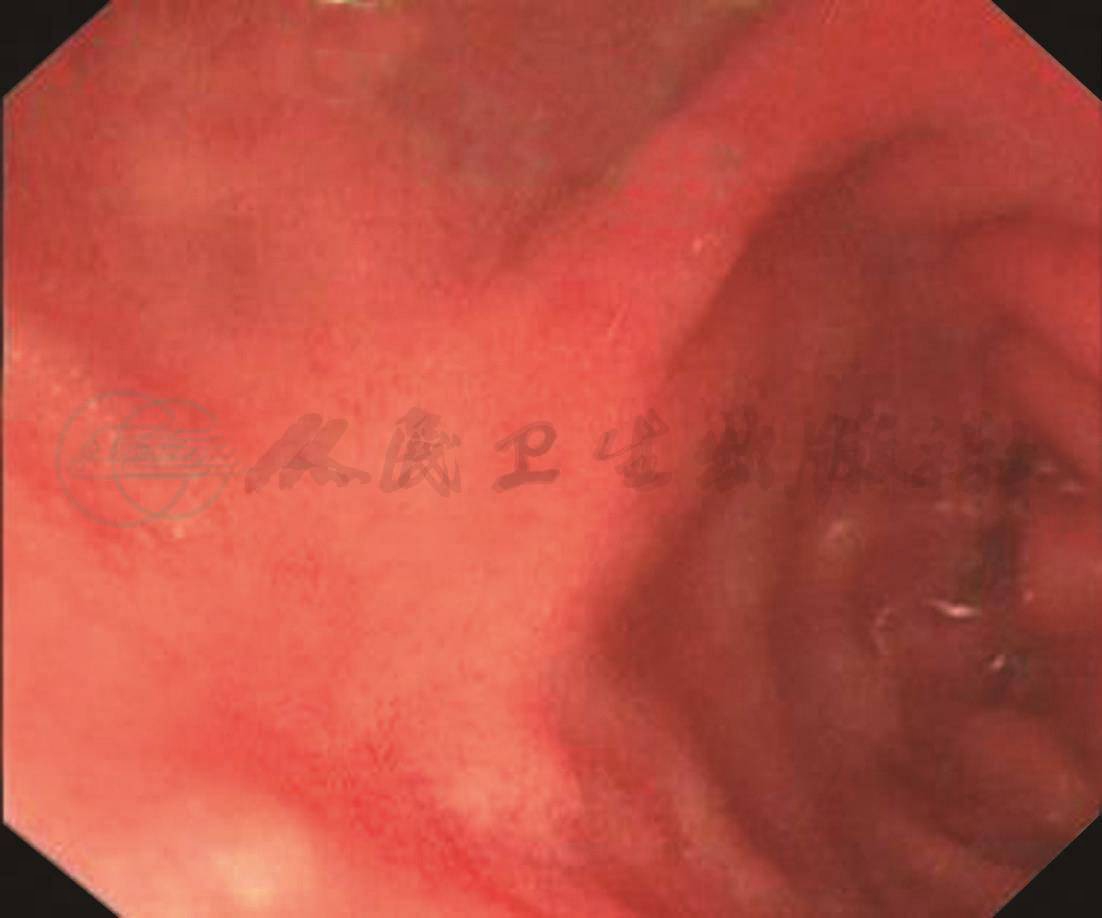

入院后给予快速补液、抑酸、止血等治疗,患者又再呕吐暗红色血样物约300ml,测生命体征平稳,行急诊胃镜检查,发现胃腔内大量暗红色血液潴留,进镜至十二指肠球部,可见前壁一巨大血凝块,并有活动性渗血,用水冲洗血凝块,无法有效清除血凝块,仍无法暴露出血病灶,此时患者因胃镜刺激,躁动不安,无法配合胃镜下的治疗,征得患者及家属同意后,改行插管麻醉胃镜,此次检查,先于胃镜头端安置透明帽,再次进镜至十二指肠球部出血处,采用负压吸引法,将血凝块吸出,对病灶处反复用水冲洗,暴露出一个1.0cm×1.0cm的溃疡病灶,伴活动性渗血,依据Forrest分级,将其分为Forrest Ⅰb级,我们采用黏膜下注射肾上腺素+氩离子凝固止血术。经治疗,患者出血停止。术后给予抑酸、护胃治疗,于第6天复查胃镜,见溃疡表面覆白苔,无活动性出血;于第28天复查胃镜,溃疡呈愈合期改变,于第56天复查胃镜,溃疡呈瘢痕期改变(图1)。

C.内镜头端带透明帽,吸出血凝块,明确病灶(Forrest Ⅰb级)

G.6天及28天后内镜复查见溃疡愈合及瘢痕形成

H.6天及28天后内镜复查见溃疡愈合及瘢痕形成

I.6天及28天后内镜复查见溃疡愈合及瘢痕形成

图1 内镜下诊治过程